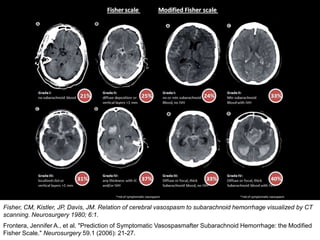

Modified Fisher scale on CT brain (predict risk of vasospasm):

Risk of vasospasmIVHSAH

24%-No or minimalGrade I

33%+MinimalGrade II

33%-Diffuse focal or thickGrade III

40%+Diffuse focal or thickGrade IV

Frontera, Jennifer A., et al. "Prediction of Symptomatic Vasospasmafter Subarachnoid Hemorrhage: the Modified

Fisher Scale." Neurosurgery 59.1 (2006): 21-27.

Fisher, CM, Kistler, JP, Davis, JM. Relation of cerebral vasospasm to subarachnoid hemorrhage visualized by CT

scanning. Neurosurgery 1980; 6:1.